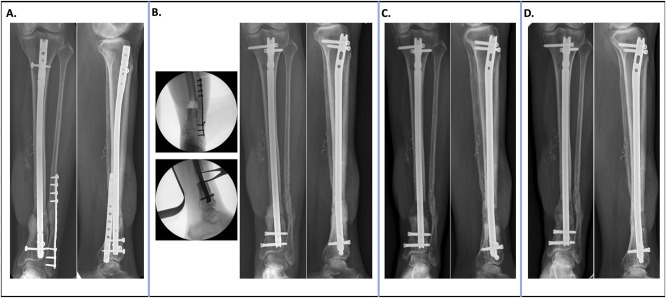

Infection and chronic post-traumatic osteomyelitis of the tibia after open fracture are complex problems that cause significant morbidity and threaten the viability of a limb. Therefore, it is of utmost importance for the orthopaedic surgeon to understand both patient and treatment factors that modify the risk of developing these disastrous complications. Infection risk is largely based on severity of open injury in addition to inherent patient factors. Orthopaedic surgeons can work to mitigate this risk with prompt antibiotic administration, thorough and complete debridement, expedient fracture stabilization, and early wound closure. In the case osteomyelitis does occur, the surgeon should use a systematic multidisciplinary approach for eradication.